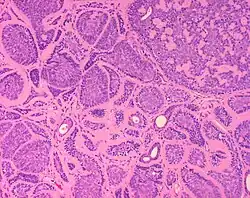

Micrograph of a dermal cylindroma in H&E stain. -

Micrograph of dermal cylindroma in H&E stain. -

Dermal cylindromas are:

- Dermal lesions consisting of nests of cells that are surrounded by hyaline (i.e., glassy, eosinophilic, acellular) material and have:

- Hyperchromatic nuclei that may palisade (columnar nuclei arranged around the periphery of the cell nests with their short axis tangential to the nest periphery), and

- Cells with lighter staining ovoid nuclei at their centre.

They lack of a significant number of lymphocytes; this differentiates them from spiradenomas.